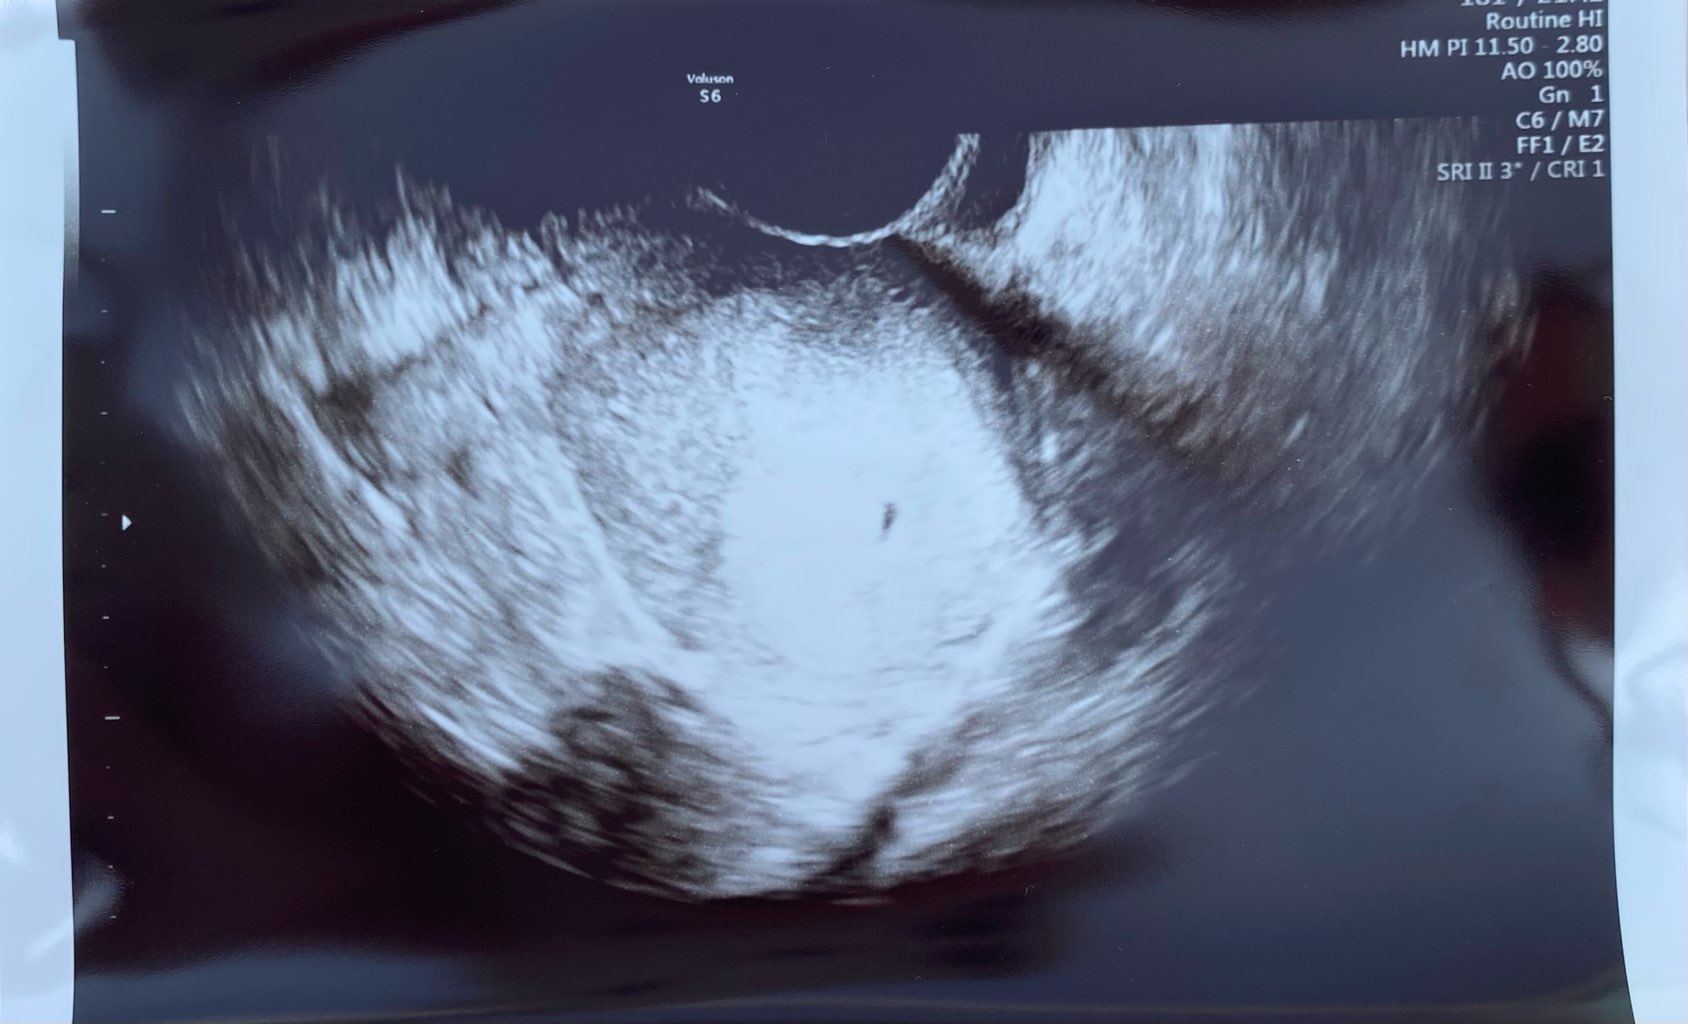

Hej dziewczyny, ja już po wizycie

Widzicie ten maleńki kropek?

Pęcherzyk umiejscowiony bardzo ładnie po środku, piękne endometrium.

Wszystko jak powinno być

Niepotrzebnie spanikowałam z tsh, podobno nie jest najgorsze, dawka leku pozostaje bez zmian na chwilę obecną

Następna wizyta z początkiem lipca![]()